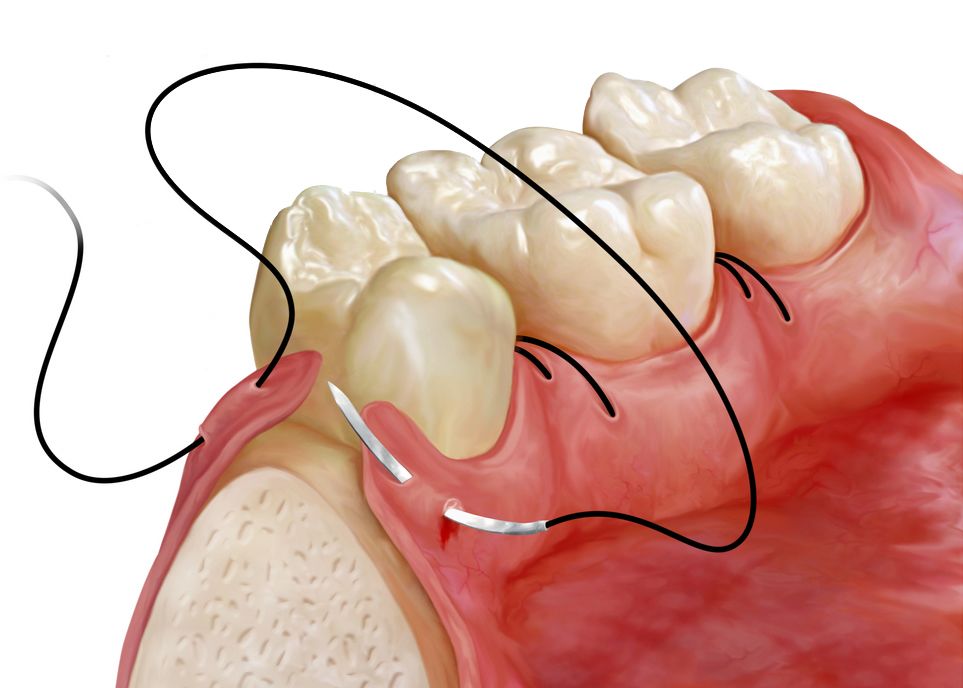

Flap Surgery

Patients with advanced gum disease may require flap surgery if more conservative periodontal treatments such as scaling and root planing are not sufficient. This procedure provides access to the roots and underlying structures that support the teeth to remove plaque and tartar and smooth bone.